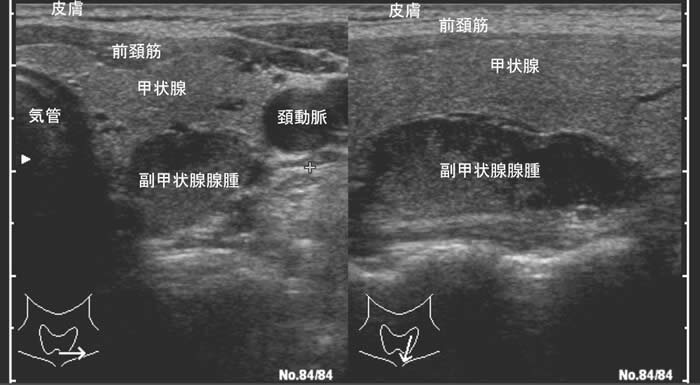

次に4つある副甲状腺のどれが腫れているかを、画像診断で調べます。最初は頚部超音波検査が、痛みのまったくない検査で精度も高いので第一選択として行われます。特殊なアイソトープ検査(99mTc-MIBI シンチグラムという検査)も診断精度の高い検査です。その他の検査方法として、頚部・縦隔CT検査、MRI検査などが行われます。

頚部超音波検査